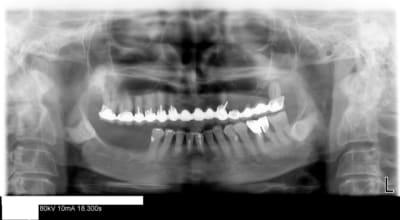

> J'ai ma pano (faite en janvier) je sais qu'il me faut faire l'endo de la 18 pour

> l'inclure sous un bridge de 18 à 15 pour remplacer 16 mais on m'a parlé

> d'implant et je ne sais plus quoi faire !!

J'aurais vraiment été heureux d'avoir une patiente qui sait déja ce qu'on doit lui faire, et en plus avec sa pano sous le bras

sans doute un petit scan 3d, et aprés on discute, et de toute façon on va faire comme pour nous même, car tu es de la famille